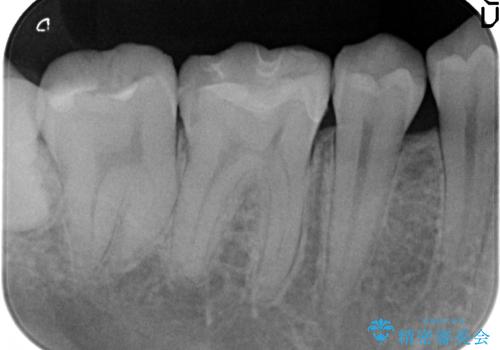

- 右下の銀歯が気になるといらっしゃった方の症例です。

右下6番目の銀歯を除去後、セラミックインレーによる修復を行いました。

当院のセラミックインレーはemaxという強度と審美性に優れた材料を使用しています。

またプレス方式でインレーを製作しているため、削り出しで製作するCADCAMより優れた適合性も持ち合わせており、虫歯が再発しにくい修復物です。